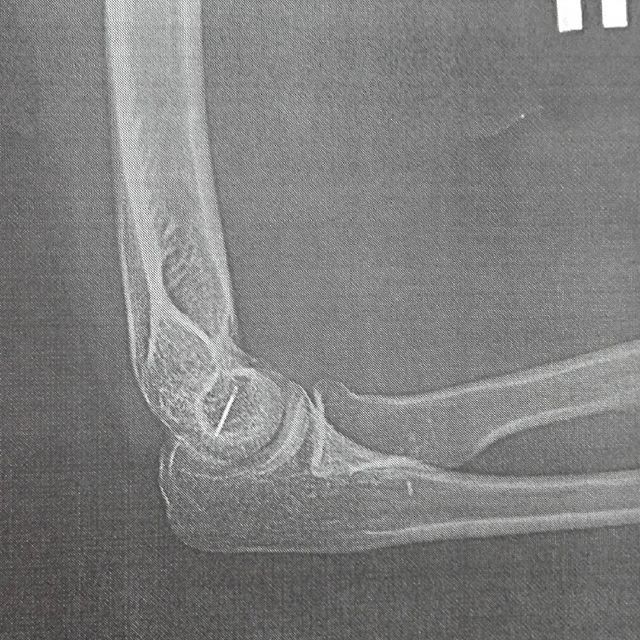

Иголка у основания плечевой кости

Интересная ситуация произошла вчера. Ложилась я спать и значит легла локтем на что-то острое. Я как настоящая женщина начала паниковать, но меня успокоили, мол, не может быть, случай на миллион, засыпай. Но не тут-то было, заставила парня прочесать всю кровать и вуаля, он нашел иголку без наконечника!

Поехали мы значит в травму, а она закрыта:( Поехала в больницу, меня выгнали, мол много людей, езжайте в другую травму, а потом приезжаете. Я не сдалась и поехала. Да, ее нашли, разрезали пол локтя под Новокаином и не достали.

"Езжайте в больницу, вам под современными аппаратами все сделают". Приезжаем, проходим адовые анализы из разряда :"Гепатит, Туберкулез, Вич, Спид". И наконец нас принимают.

Самое смешное здесь ребятки, что мне говорят, мол "Свободна до понедельника, в порядке очереди". Вот, лежу дома, и боюсь, как бы игла не пробралась дальше. Не успокоите?)